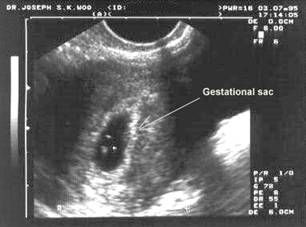

В ранние сроки беременности на эхограммах четко отображается матка (рис 1), содержащая овальной формы плодное яйцо с достаточно утолщенной стенкой, внутренний диаметр которого 0,5 см, а наружный до 1,5 – 1,6 см (3-4 недели), включая яркую полосу ворсинчатого хориона. К 6 неделям плодное яйцо занимает ½ плоско-

(рис. 1) Плод в 4 недели, вагинальное исследование. сти матки, в нем видны контуры